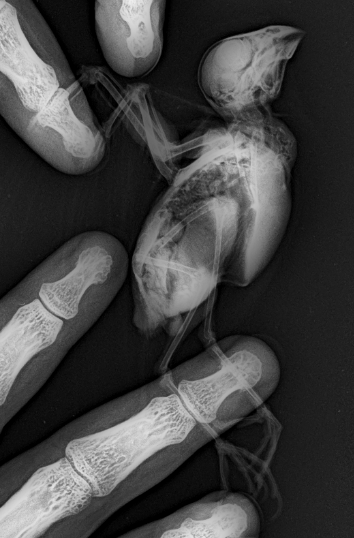

Съездила туда куда вы сказали, предложили лечить антибиотиками рандомную патогенную заразу, без забора материалов на анализы. Сделали рентген, снимки не очень конечно, кенарок дрожал как кленовый лист, но может кто что разберет, да скажет что в нем может быть не так? image.png.efe985181302db6fb05ce77649cd80d2.pngimage.png.cfa14bf141251b7387127fa364deba62.png